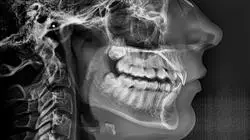

O manejo da Endodontia e da Periodontia como os tratamentos mais importantes para o cuidado e a prevenção da saúde bucal é fundamental para qualquer profissional da área odontológica. Graças ao uso dessas duas técnicas, é possível manter as gengivas em boas condições e, ao mesmo tempo, garantir o tratamento de doenças pulpares na raiz dos dentes causadas por infecções ou traumas e as possíveis complicações derivadas de cada uma delas. Os muitos avanços que foram feitos nesse campo permitiram o uso de materiais e ferramentas sofisticados e específicos, contribuindo para o fornecimento de um serviço cada vez mais especializado e de qualidade.

Desde 1963, a Associação Dental Americana reconheceu o tratamento de canal ou endodontia como uma especialidade no campo odontológico. Essa decisão não foi, é claro, fortuita, uma vez que o procedimento em si exige habilidades bastante refinadas, minuciosas e precisas para obter um resultado bem-sucedido. A periodontia, por sua vez, requer conhecimentos específicos para diagnosticar e tratar cirurgicamente patologias periodontais que podem surgir até mesmo de uma má oclusão dental. Com o objetivo de reunir essas duas disciplinas e compilar seus fundamentos, conceitos e práticas em um único material instrutivo e exclusivo, a TECH Universidade Tecnológica desenvolveu o Programa Avançado de Endodontia e Periodontia: uma capacitação totalmente virtual que concederá ao dentista comum a credibilidade curricular necessária para atuar com confiança e habilidade em áreas desafiadoras. Estamos convencidos de que a busca pela excelência não é alcançada apenas com os fundamentos de uma carreira acadêmica; na TECH, nos especializamos em formar profissionais que superem os padrões médios. Você gostaria de alcançar o mais alto nível de desempenho em sua profissão? Estude conosco e perceba a diferença.

Os tempos estão evoluindo a passos largos. Sabe-se que por volta de 700 a.C., os etruscos usavam pedaços de marfim e conchas marinhas para fazer implantes dentários. Hoje em dia, os avanços tecnológicos permitem que os profissionais de saúde bucal realizem intervenções de maneira muito mais confortável e versátil. A Implantologia, por exemplo, permitiu avanços nos estudos de periodontologia, bem como nos tratamentos de regeneração óssea e regeneração tecidual guiada. Você possui as habilidades necessárias para realizar esses procedimentos com total segurança? Nossa pós-graduação fornecerá as ferramentas teóricas e práticas para isso, assim como as atividades dos endodontistas, cujo campo carece de profissionais versados devido ao alto grau de dificuldade exigido por uma intervenção desse tipo. É necessário saber realizar diagnóstico, anestesia, preparação, abertura, condução, obturação e controle. No Programa Avançado que oferecemos, você poderá dominar essas competências com facilidade e flexibilidade, graças ao nosso sistema de educação virtual excepcional.